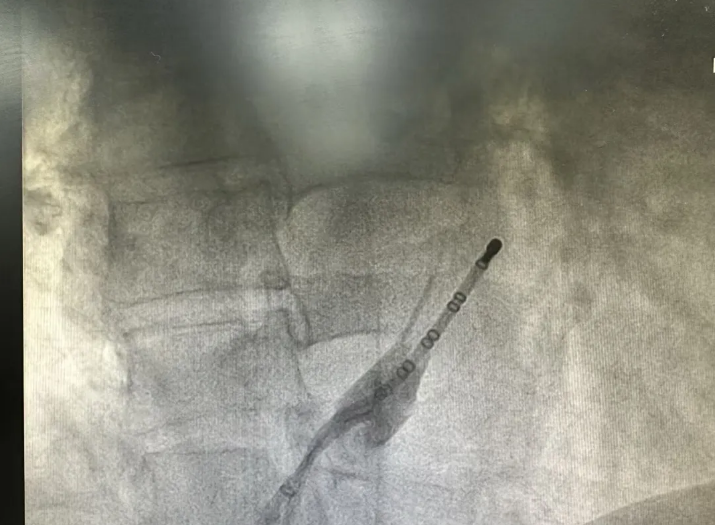

通过向Marshall静脉注入无水酒精,利用化学作用精准灭活该静脉相关的异位起搏点与传导通路,消除房颤触发源,弥补单纯射频消融在细微病灶、血管旁区域的治疗盲区。

在电生理三维系统指导下,对左房及肺静脉进行三维重建、基质标测,双侧肺静脉、二尖瓣峡部、三尖瓣峡部进行射频消融,实现电位隔离、双向阻滞,巩固消融效果,降低复发风险。手术过程顺利,术后患者恢复窦性心律,心律稳定,生命体征平稳,未出现并发症,已康复出院。